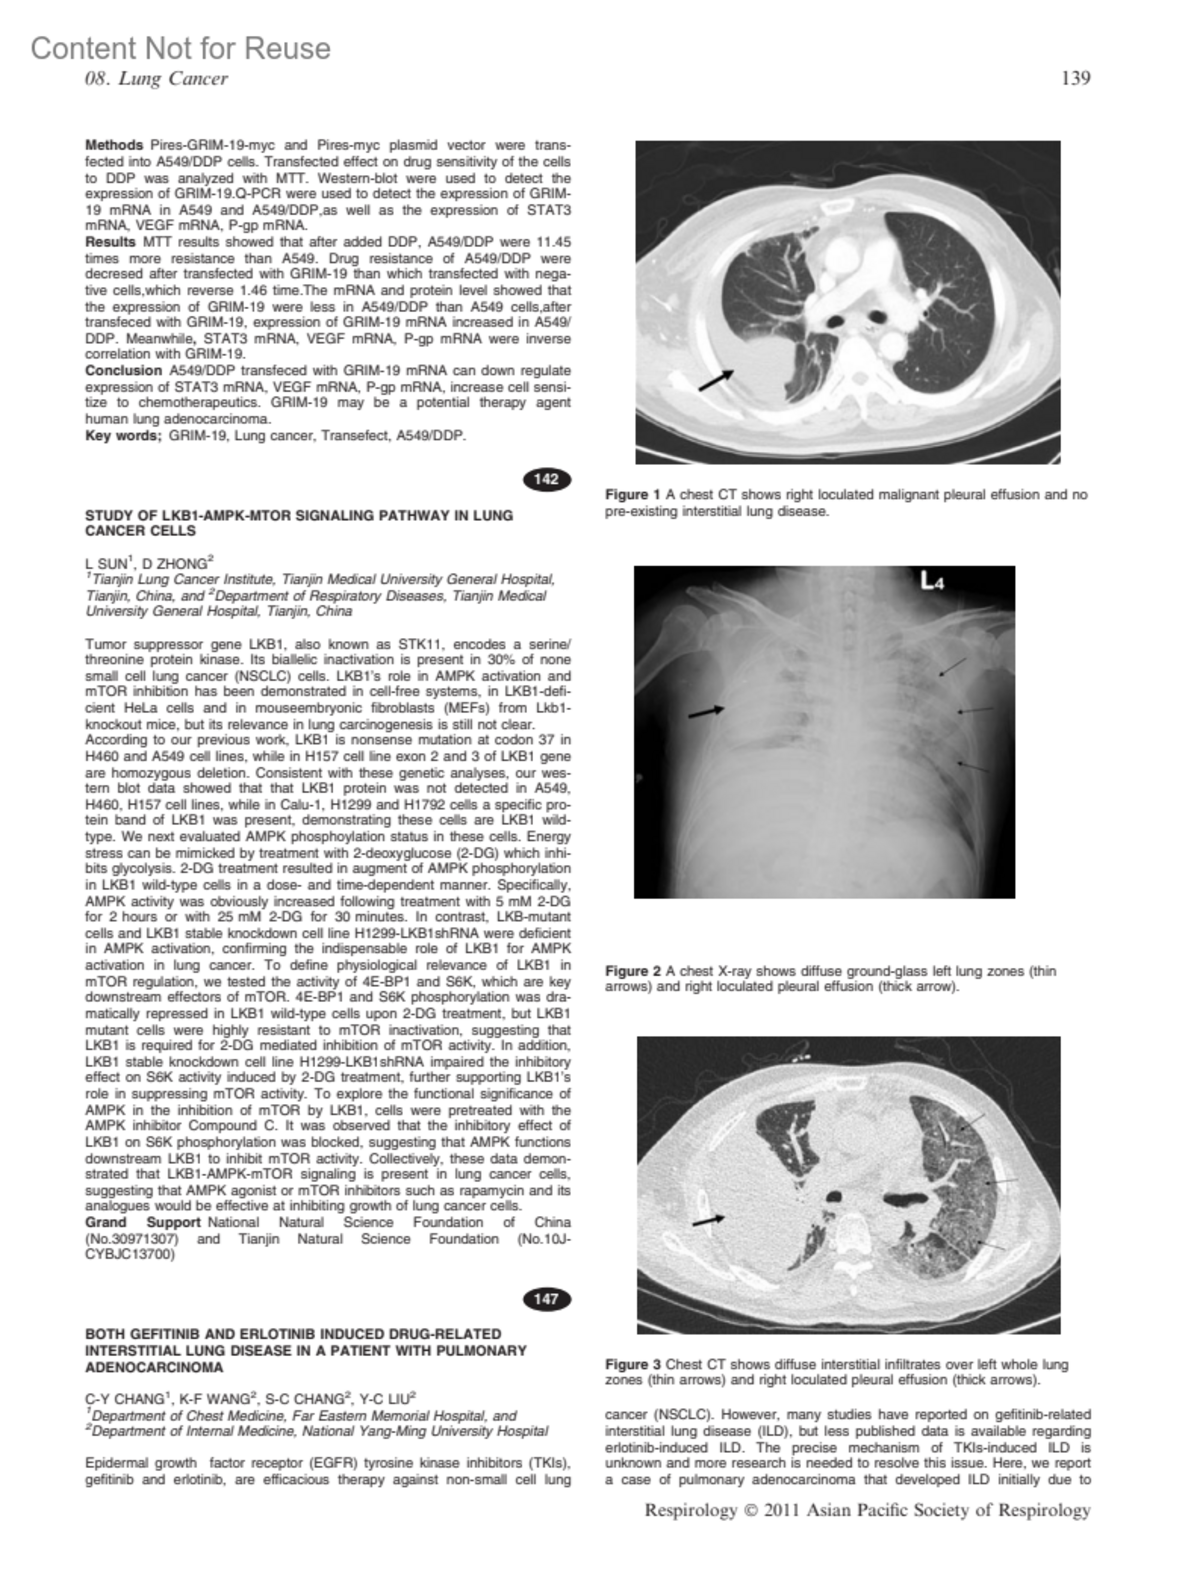

BOTH GEFITINIB AND ERLOTINIB INDUCED DRUG-RELATED INTERSTITIAL LUNG DISEASE IN A PATIENT WITH PULMONARY ADENOCARCINOMA147CHANG, C-YWANG, K-FCHANG, S-CLIU, Y-CAuthor information1Department of Chest Medicine, Far Eastern Memorial Hospital, and 2Department of Internal Medicine, National Yang-Ming University HospitalRespirology 16:p 139-140, November 2011.Copyright © 2011 Blackwell Publishing Ltd.